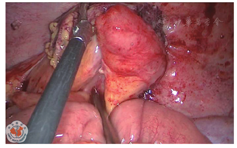

患者女,40岁,身高160 cm,体质量52 kg,因2 d前无明显诱因出现左下腹部持续性绞痛,于2018年10月19日急诊入院,体温37.7℃,脉搏112次/分,伴稍恶心,无呕吐、放射痛、发热,无腹泻、血便,无尿频、尿痛等症状。1 d前曾在当地社区医院以"急性肠炎"给予抗感染、解痉等治疗,自觉症状有所缓解,次日午间症状再次加重。查体:左下腹压痛(+)、反跳痛(+),局部腹肌紧张明显。行腹部CT平扫检查示:结肠走行反位,右半结肠位于左上腹,阑尾增粗伴周围渗出,周围间隙模糊,阑尾最粗约1.7 cm,临近盲肠壁稍增厚;胃腔大部分位于右侧,十二指肠垂直下行,可见Ladd束带;肝脏体积明显增大;脾脏受推挤,位于左侧肾上腺前方(图1,图2,图3)。诊断为"结肠反位,阑尾炎累及盲肠"。血常规检查示:白细胞计数8.81×109/L,中性粒细胞百分比79.5%。综合各项检查结果,诊断为"急性肠旋转不良型左侧阑尾炎",遂于当夜急诊行腹腔镜下异位阑尾切除术。腔镜探查示盆腔内大量积脓,大网膜覆盖左侧回盲部,乙状结肠位于盆腔右侧,肝左叶明显增大并覆盖脾脏,胆囊仍位于右侧,切除阑尾及网膜组织大小约8.0 cm×6.0 cm×2.5 cm(图4,图5,图6,图7)。

腹腔镜手术或开腹探查手术是治疗左侧阑尾炎的主要方式。由于术前已考虑为左侧阑尾炎,故腔镜Trocar放置位置为常规位置的镜像旋转,脐上置10 mm Trocar,右侧腹壁及右下腹壁分别置入5 mm及12 mm Trocar,为方便右手操作以he-mo-lock夹夹闭阑尾根部,右下腹麦氏点所置Trocar为12 mm,其他手术操作过程与常规腹腔镜下阑尾切除术无异。